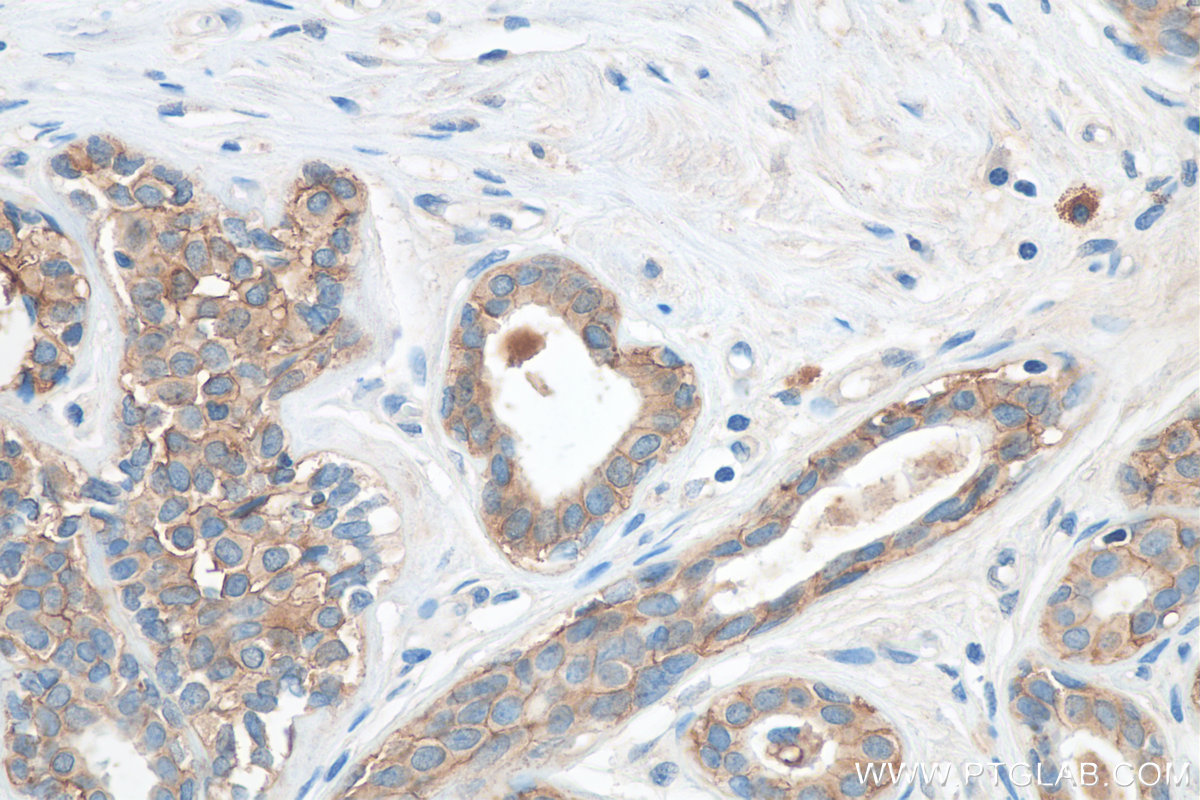

| Positive IHC detected in | human breast cancer tissue, human prostate cancer tissue Note: suggested antigen retrieval with TE buffer pH 9.0; (*) Alternatively, antigen retrieval may be performed with citrate buffer pH 6.0 |

| Immunohistochemistry (IHC) | IHC : 1:50-1:500 |

27360-1-AP targets TACSTD2/TROP2 in WB, IHC, IF/ICC, ELISA applications and shows reactivity with human samples.

Trophoblast cell surface antigen 2 (TROP2), also named as TACSTD2, is a transmembrane glycoprotein. TROP2 plays a role in transducing intracellular calcium signals. It is expressed in trophoblast cells, cornea and multi-stratified epithelia. TROP2 is overexpressed in most carcinomas and is involved in cancer proliferation, migration, invasion, and metastasis. Congenital mutations of TROP2 cause a rare autosomal recessive disease which may lead to blindness-the gelatinous drop-like corneal disease (PMID: 35688908).